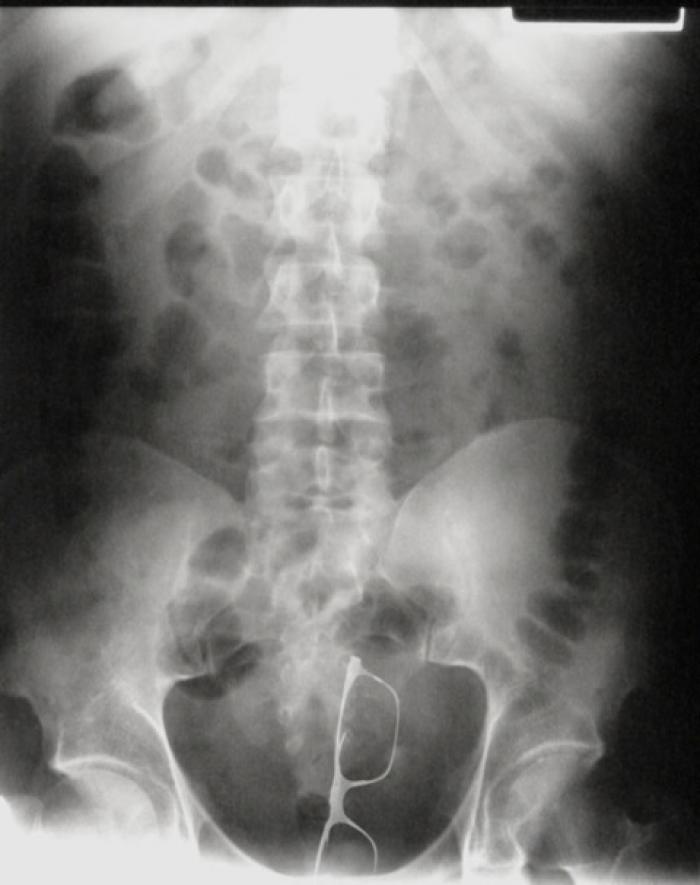

Polițiștii au parte de cele mai amuzante întâmplări, iar infractorii tind să aibă cele mai inventive modalități de a ascunde obiecte, alegând de multe ori posteriorul